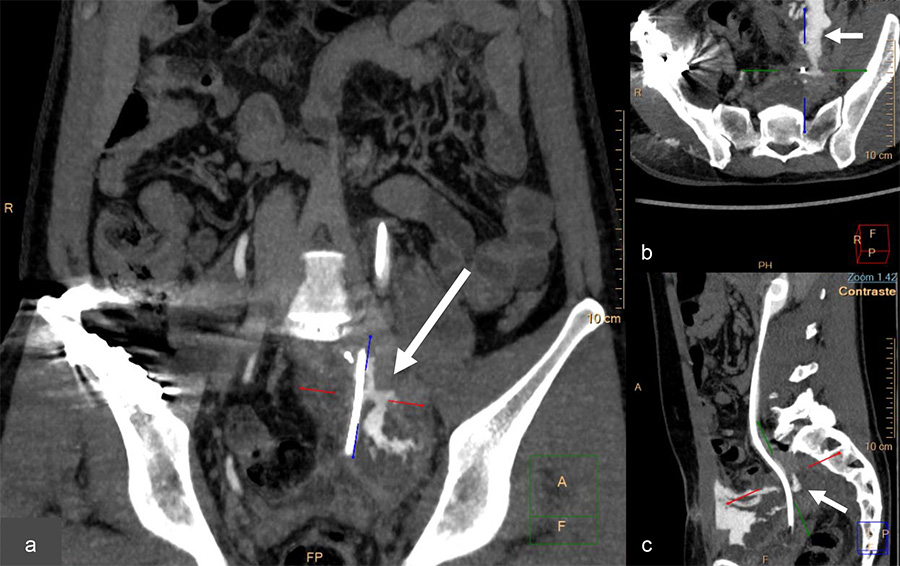

A new uroscanner reported a pelvic ureter fistula associated with a large recurrent subperitoneal urinoma (Fig. 3). This time he underwent a left ureterovesical reimplantation by a laparotomy approach, associated with IV antibiotics.